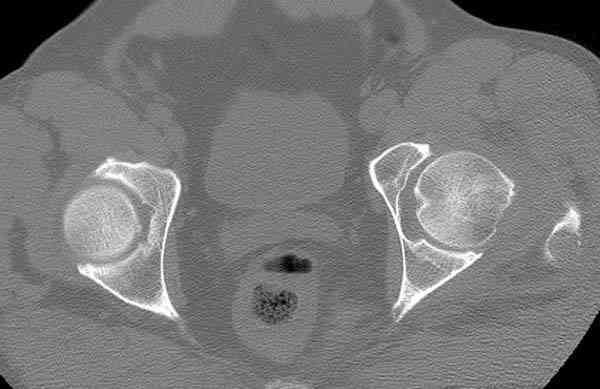

На второй день (7) обнаружен пропущенный перелом,

сделаны Компьютерная Томограмма